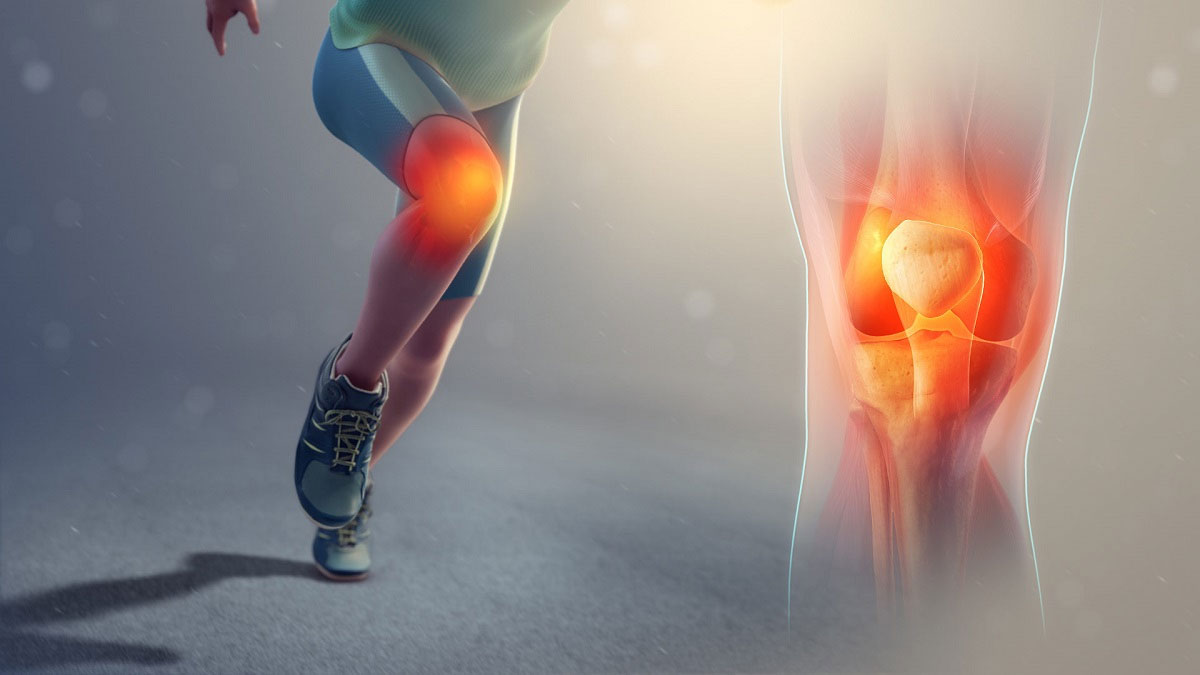

سندرم زانوی دونده (PFPS) دردی است که زیر یا اطراف کشکک زانو ایجاد میشود. متخصصان دقیق نمیدانند که علت پاتلوفمورال چیست، اما معمولاً با روش RICE (استراحت، یخ، کمپرس و بالا نگه داشتن)، فیزیوتراپی و افزایش تدریجی سطح فعالیت قابل درمان است. در این مقاله از نیاوران کلینیک به بررسی کلی سندرم پتلوفمورال میپردازیم و از علت ابتلا به آن، علائم، روشهای تشخیص، روشهای درمانی و درنهایت راههای پیشگیری از ابتلا به آن خواهیم گفت. لطفا تا انتها همراه ما باشید.

علائم سندروم پاتلوفمورال کدامند؟

از جمله نشانه های سندرم درد جلوی زانو تجربه و احساس صداهای ترکیدن یا پوپ کردن در زانوها است. سندرم درد پاتلو فمورال معمولاً به تدریج بروز مییابد و شدت درد کشکک فمورال اغلب در شرایط زیر افزایش مییابد: